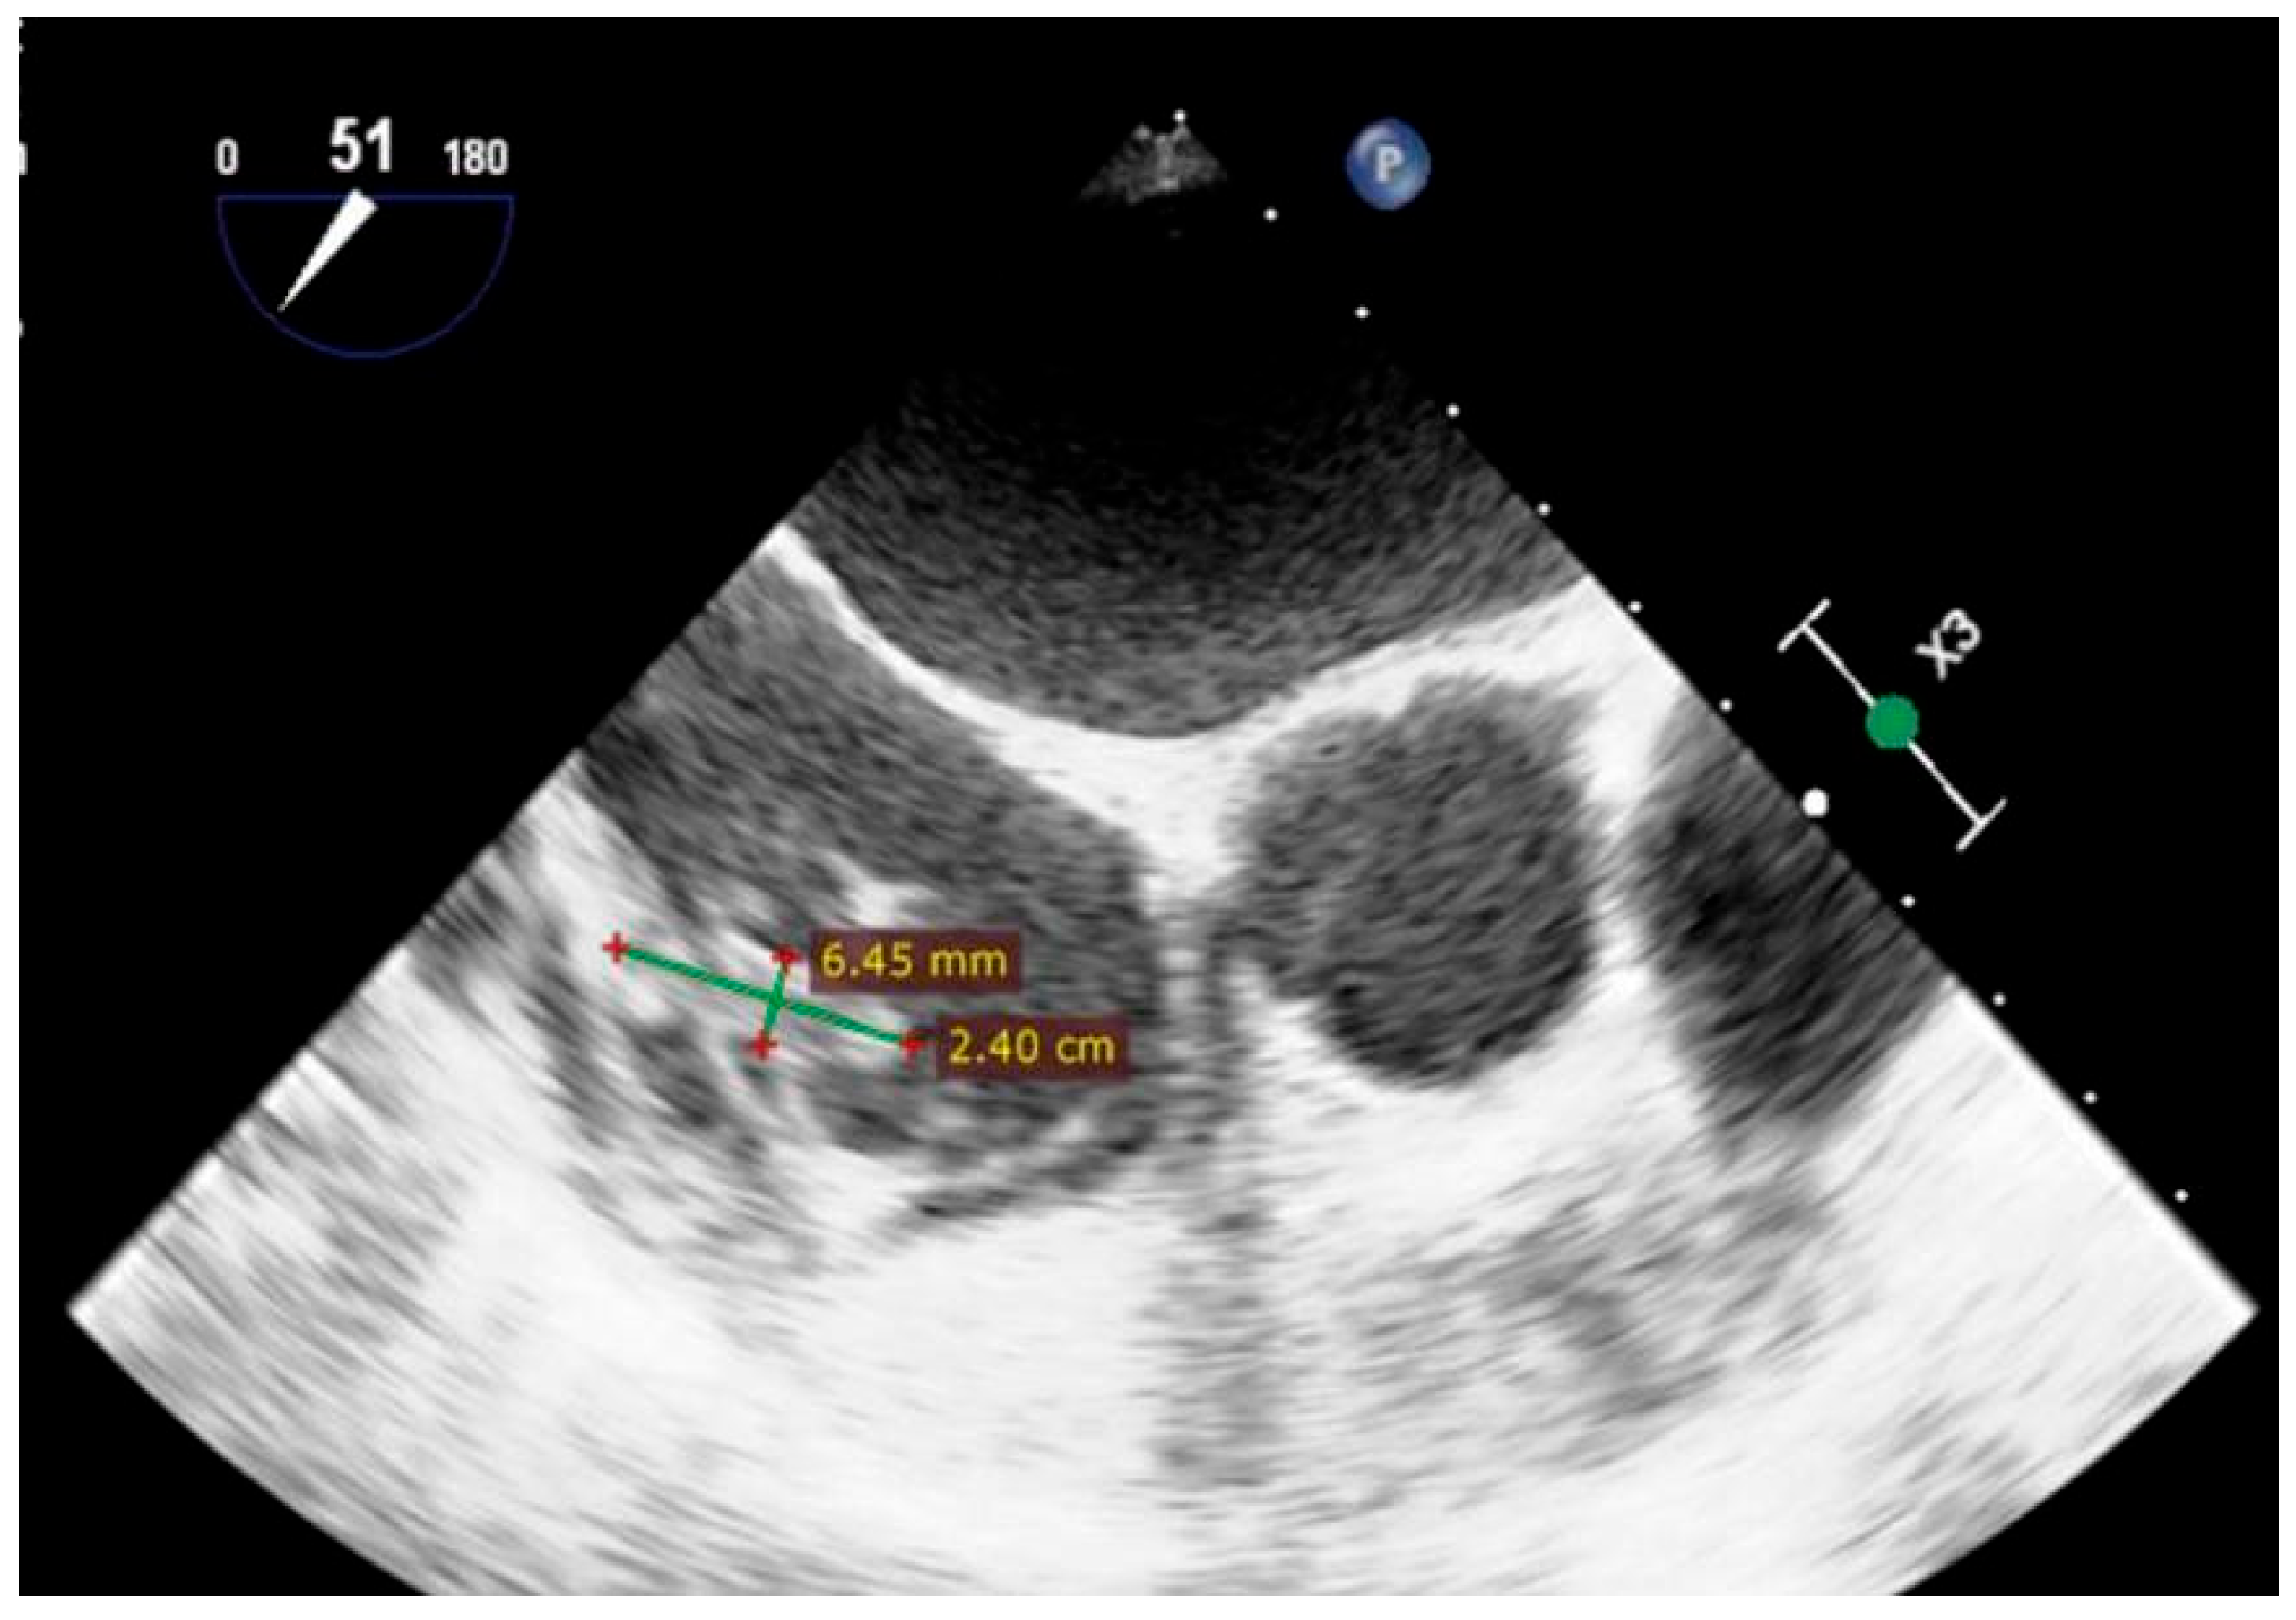

| Day 3 | Diagnosis of IE | Persistent fever, systemic inflammation | TEE: Gerbode defect with a vegetation attached near the tricuspid valve and others involving the tricuspid valve and the pacemaker lead | |

| Day 31+ | Pacemaker-related complications | Vegetation on pacemaker lead | TEE: Persistent vegetations confirmed; lead extraction via transvenous approach | Temporary external pacemaker; continued antibiotic therapy |